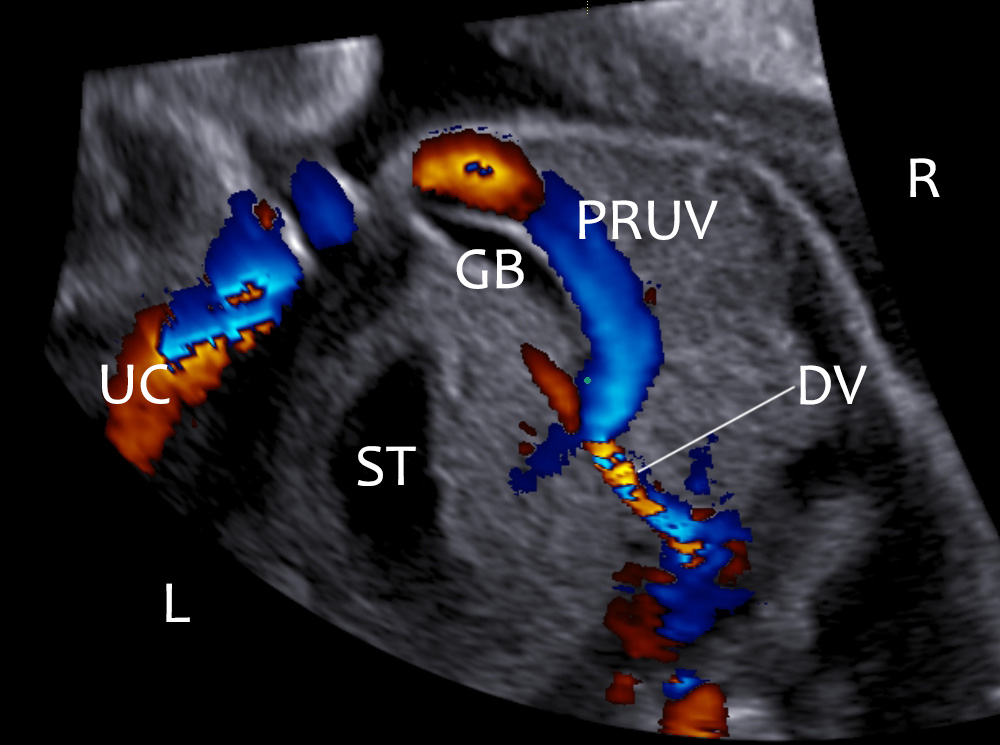

- Intrahepatic type: Umbilical vein hooks towards the stomach instead of hooking away from it.

The most common type is the intrahepatic type (about 90% of the cases). Embryologically the right umbilical vein fails to form an anastomosis with the right vitelline vein and the left umbilical vein degenerates. This creates an isolated right umbilical vein which joins the portal system at the level of the sinus venosus and there is a normal ductus venosus. (Krzyżanowski, A, et al, 2019, Weichert, J. et al, 2011).